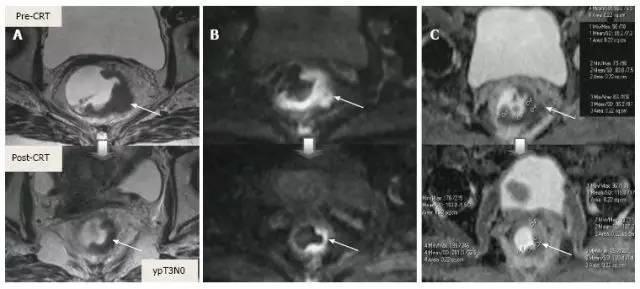

新辅助 CRT 可以降期、缩小肿瘤,减小手术范围,减少局部复发和改善生存。重新分期需比较治疗前后图像所有因素,要尽量保证图像相同条件和层面。

1.T 分期

采用传统 MRI 序列对 CRT 后肿瘤重新分期的精确性差于初始分期,尤其在证实完全缓解(yT0),主要是很难将残留的肿瘤与纤维化、水肿和正常粘膜区分开,因此 CRT 后正常的 2 层直肠壁提示为完全缓解,而残留纤维化既可以是肿瘤残留也可以是完全缓解(图 17)。

实际上 CRT 后 T2 加权 MRI 后上纤维化的信号强度很低,而残留肿瘤区域则为中等强度,仔细评估高分辨图像和 DWI 是能区分小的残留病变和纤维化的(图 18)。

图片

图 17. 新辅助放化疗后肿瘤重新分期。在不同患者的 T2 加权 MR 图像上分别显示(上:治疗前,下:治疗后)。A. 在 ypT0 直肠肿瘤中,治疗后的轴位图像显示正常的两层直肠壁(箭头),对应完全缓解;B. 在 ypT3 直肠肿瘤中,治疗后的轴位图像显示正常的双层直肠壁(箭头)。这是 MR 评估完全缓解的假阴性例子;C. 在 ypT0 直肠肿瘤中,原有肿瘤区域治疗后呈现厚的、纤维化的低信号强度疤痕(箭头)。